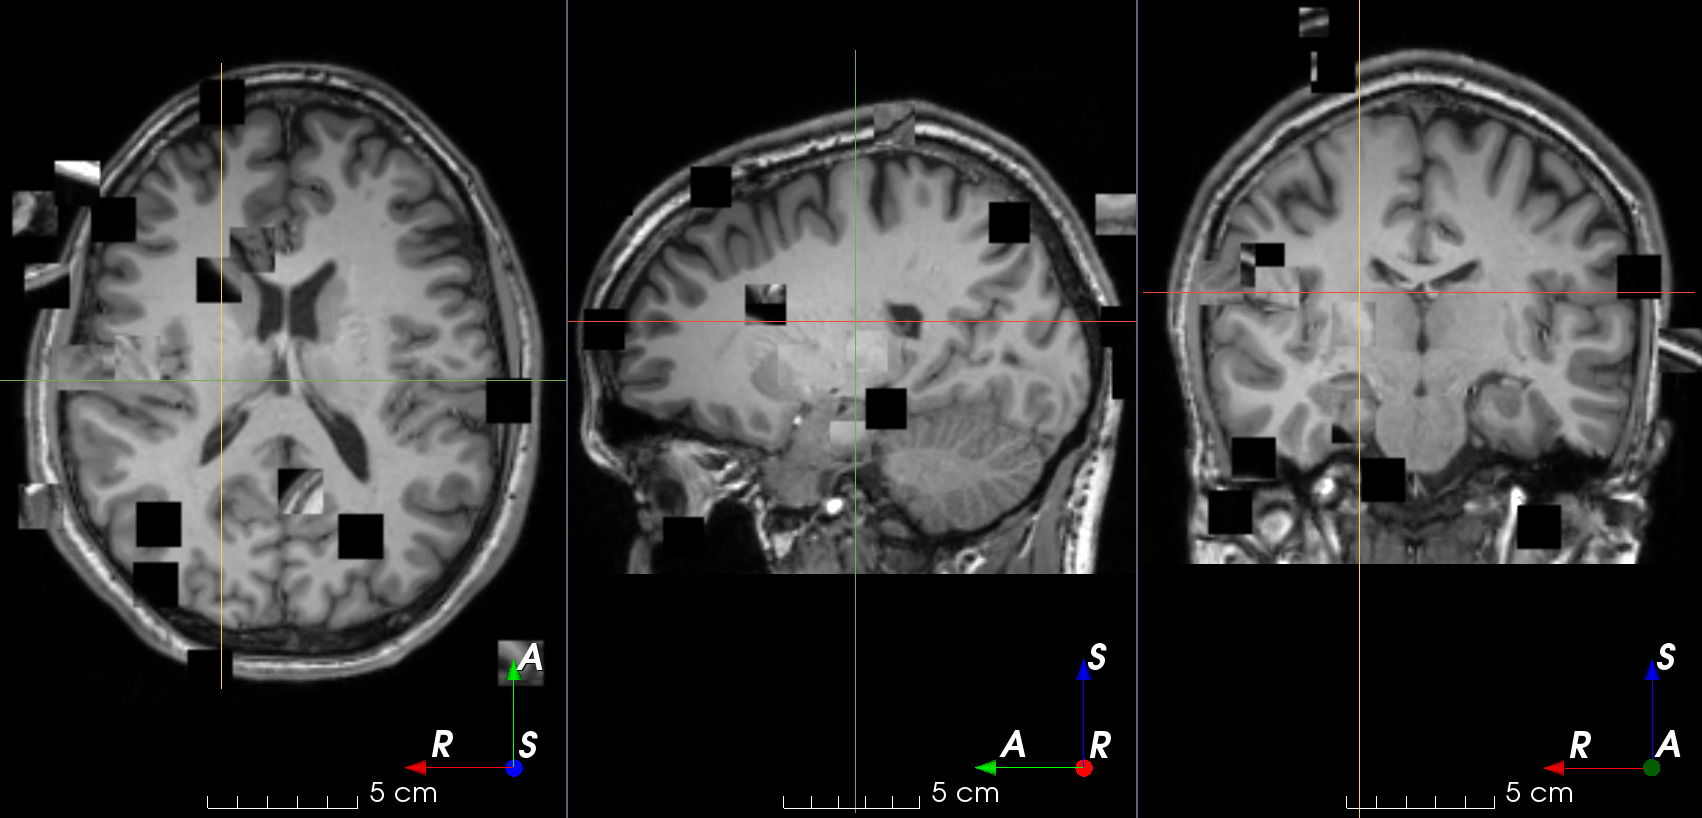

Randomly swap patches within an image.

This is typically used in context restoration for self-supervised learning .